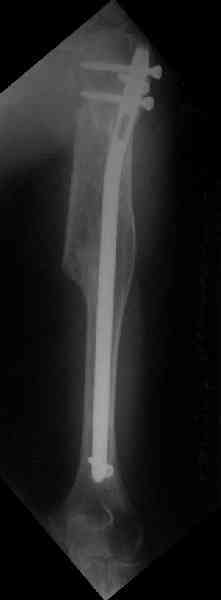

Здесь нет необходимости в серкляже. Вмешиваться на промежуточных отломках приходится, если есть угроза перфорации кожи, или промежуточный отломок попал в фасцию, как пуговица в петлю. В приложении сегментарный оскольчатый перелом плеча в проксимальном отделе, фиксированный больщеберцовым стержнем. Как видите, обошлось без серкляжа. Функция полная.

Это укороченный большеберцовый стержень, которые делает предприятие "ЦИТО".